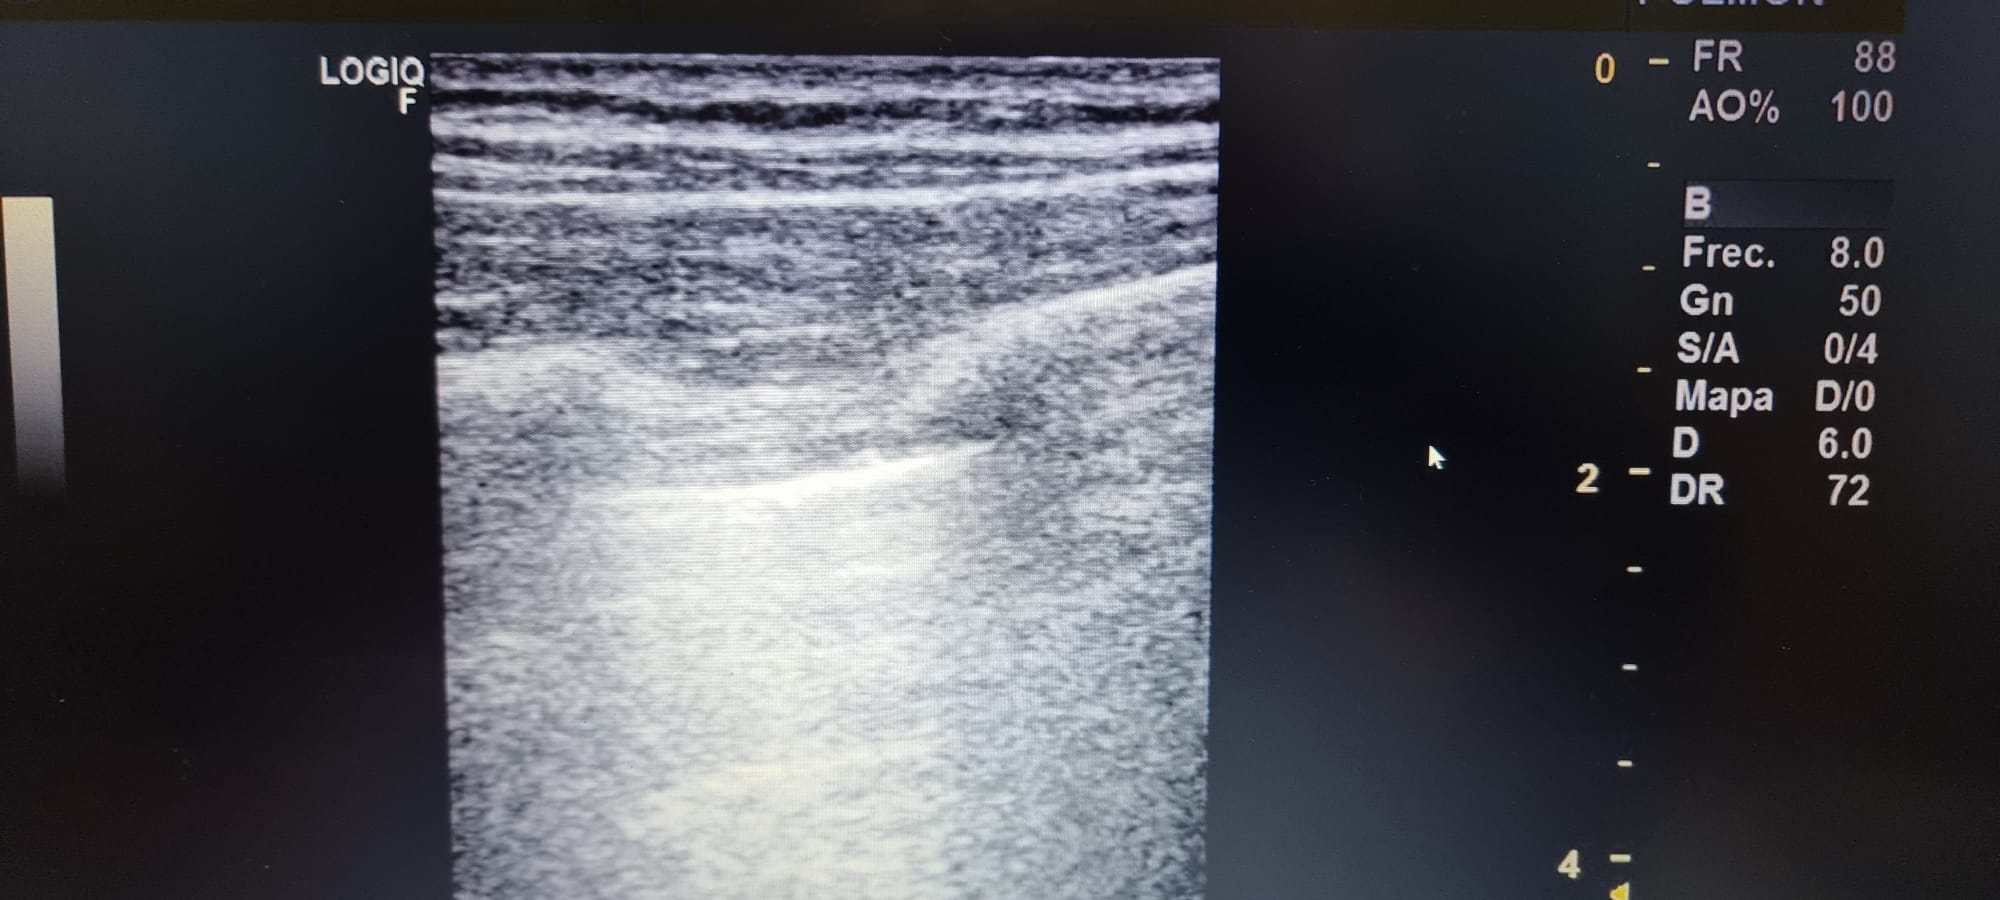

Se observa en base pulmonar izquierda defecto pleural triangullar (comparado con el contralateral).

La ecografía clínica pulmonar, nos aporta gran información que complementa la hipotesis dx, en este caso no acertada porque pensabamos mas en un TEP ya que nunca habiamos visto un derrame pleural en ecografía. Este era mínimo y no detectable con Rx Tx, con los conocimientos de la normalidad pudimos ver que había una imagen patologica comparando con el contralateral.